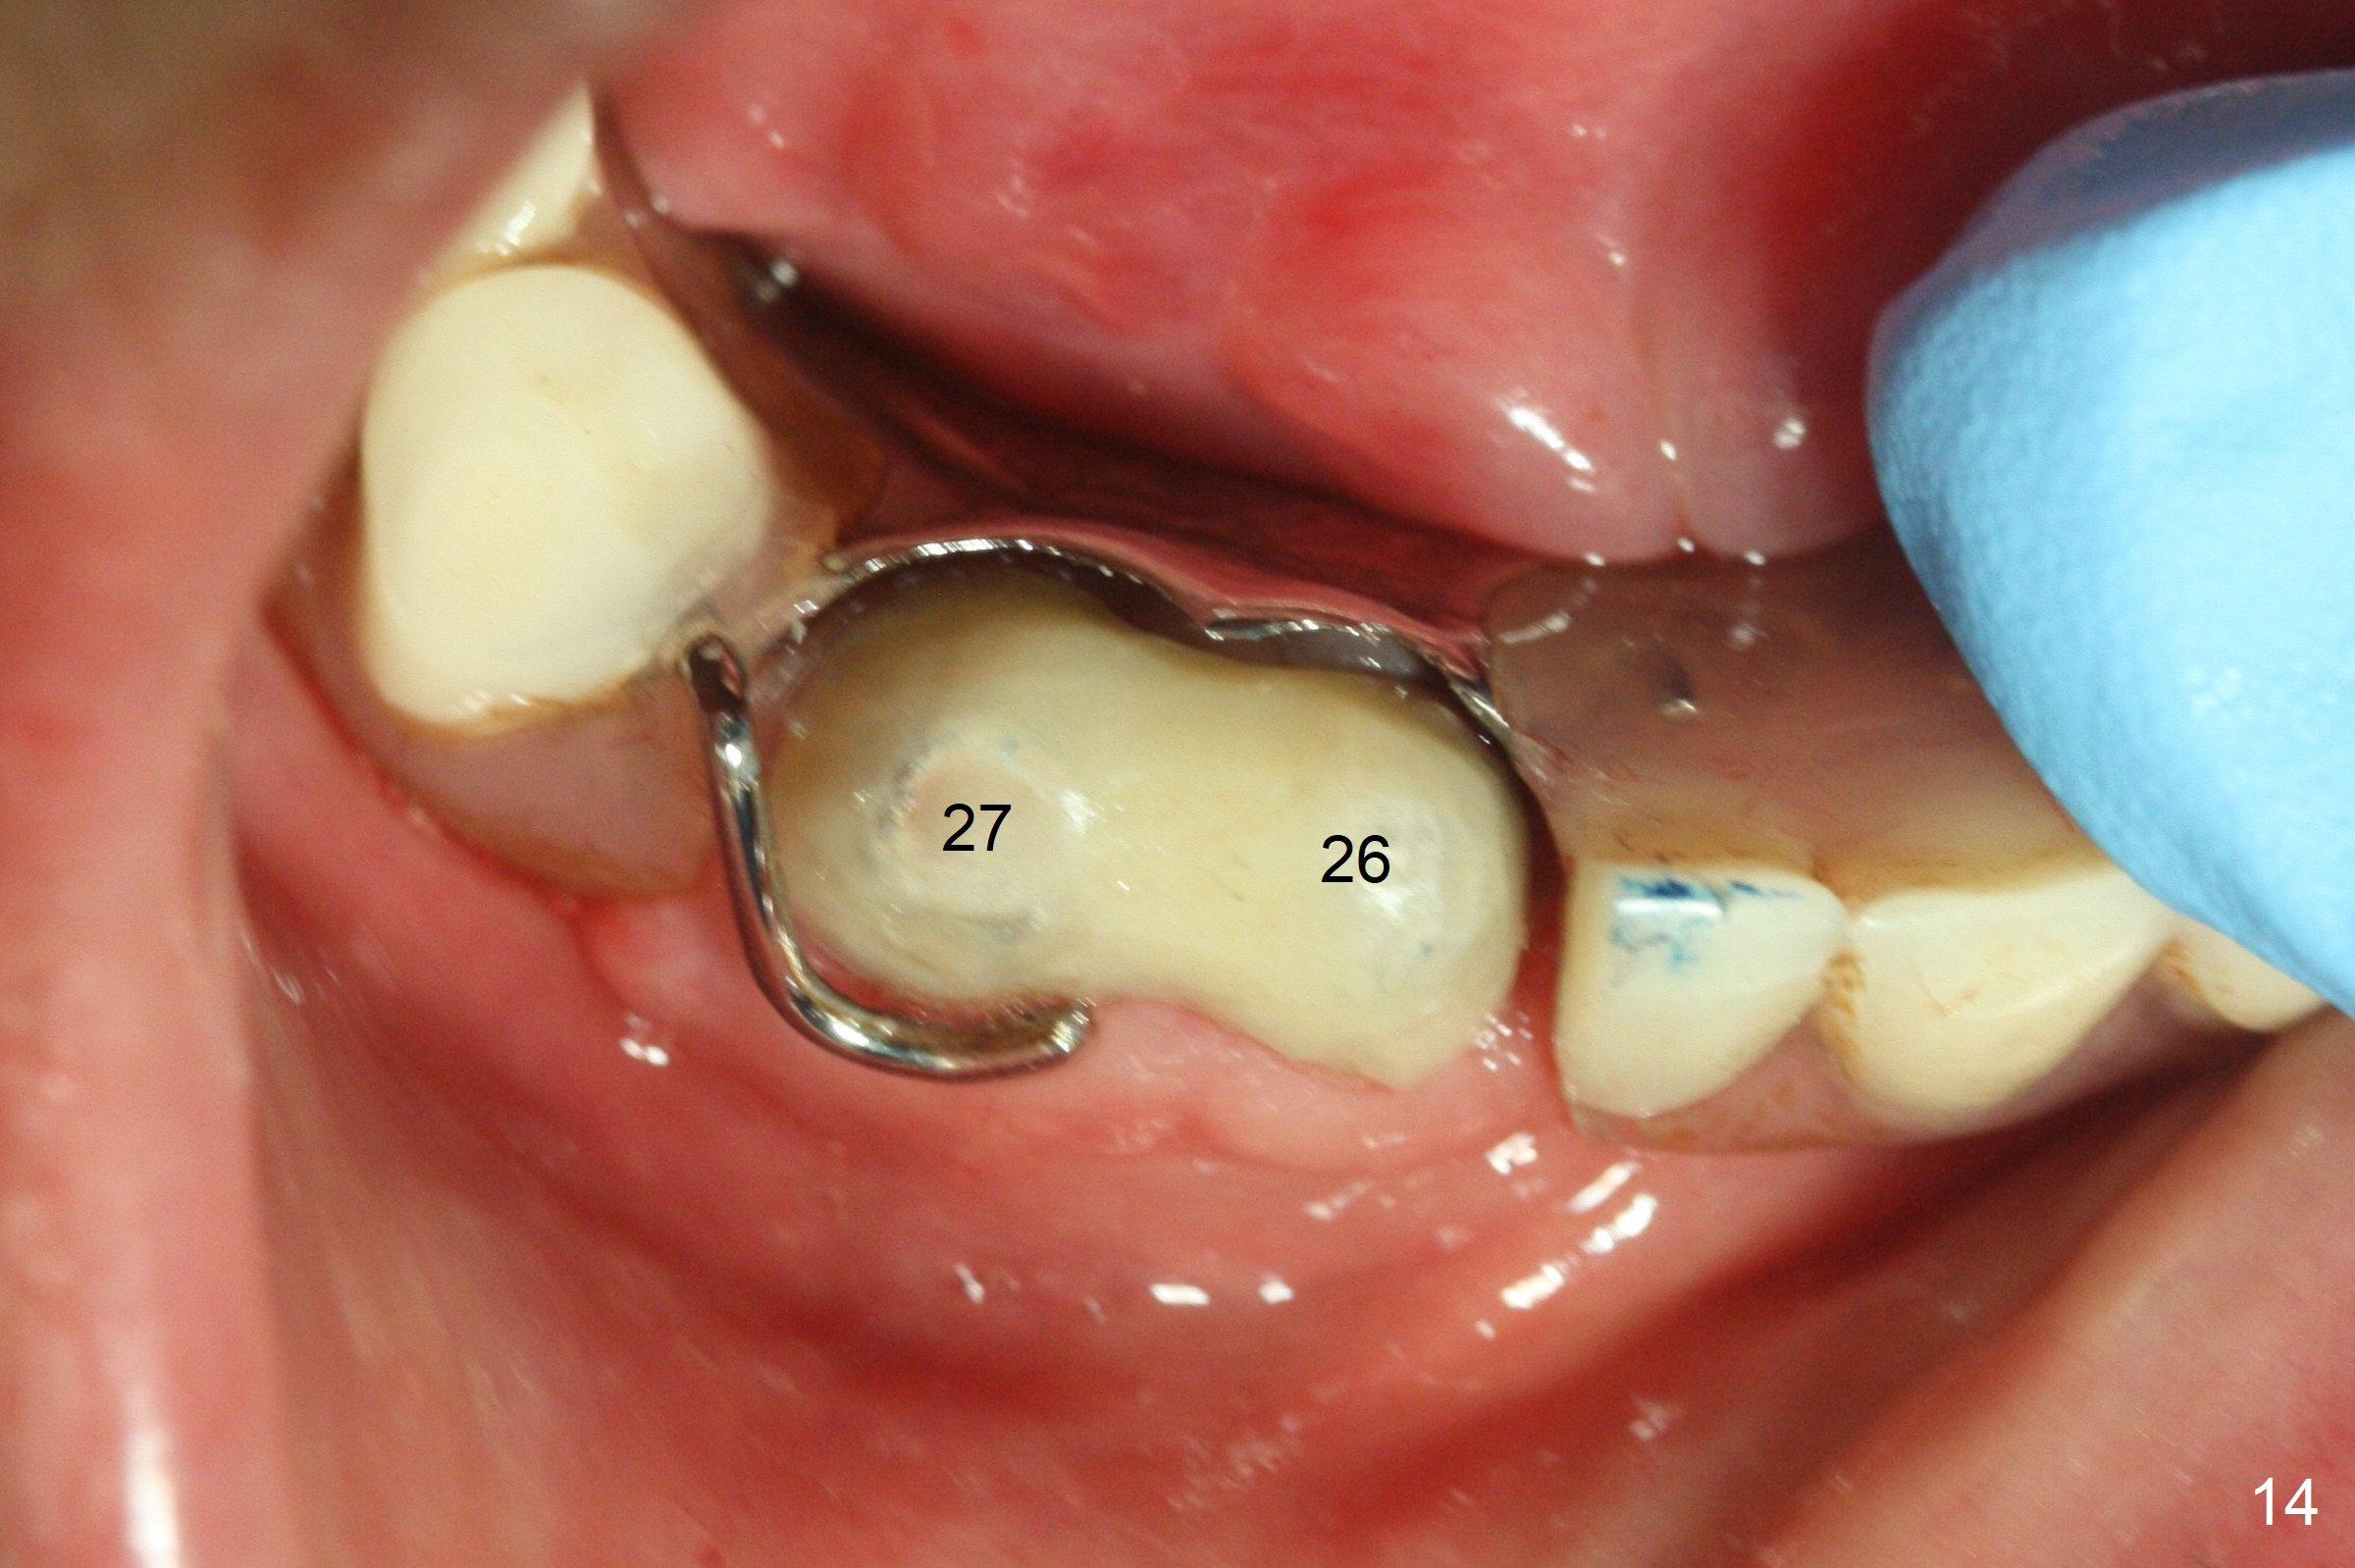

After change in abutment at #27 and abutment height adjustment at #26 and 27 (Fig.13), splinted provisional is fabricated with clearance from the RPD (Fig.14) and seal of the sockets (Fig.15). Acute submandibular and submental cellulitis develops with sublingual purulent discharge 1 month 10 days postop (Fig.16). CT confirms lingual plate perforation at both sites (Fig.17,18; red line: original socket). With block anesthesia, removal of these implants causes mild discomfort. With Hydrogen Peroxide and normal saline copious irrigation, pain reduces when anesthesia subsides. Bone graft will be placed at the sites approximately in 2 weeks. In fact the infection is not controlled until 2 weeks later (Fig.19). The clasp has to be covered with acrylic for comfort (Fig.20). The previous implant sites heal 1.5 months post implant removal (Fig.22).